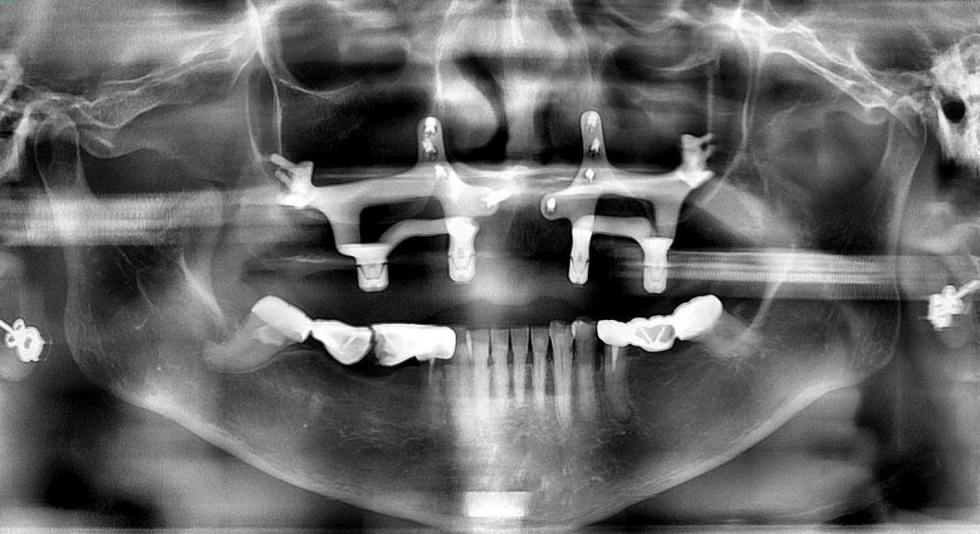

Ảnh minh họa: Ca cấy ghép implant màng xương